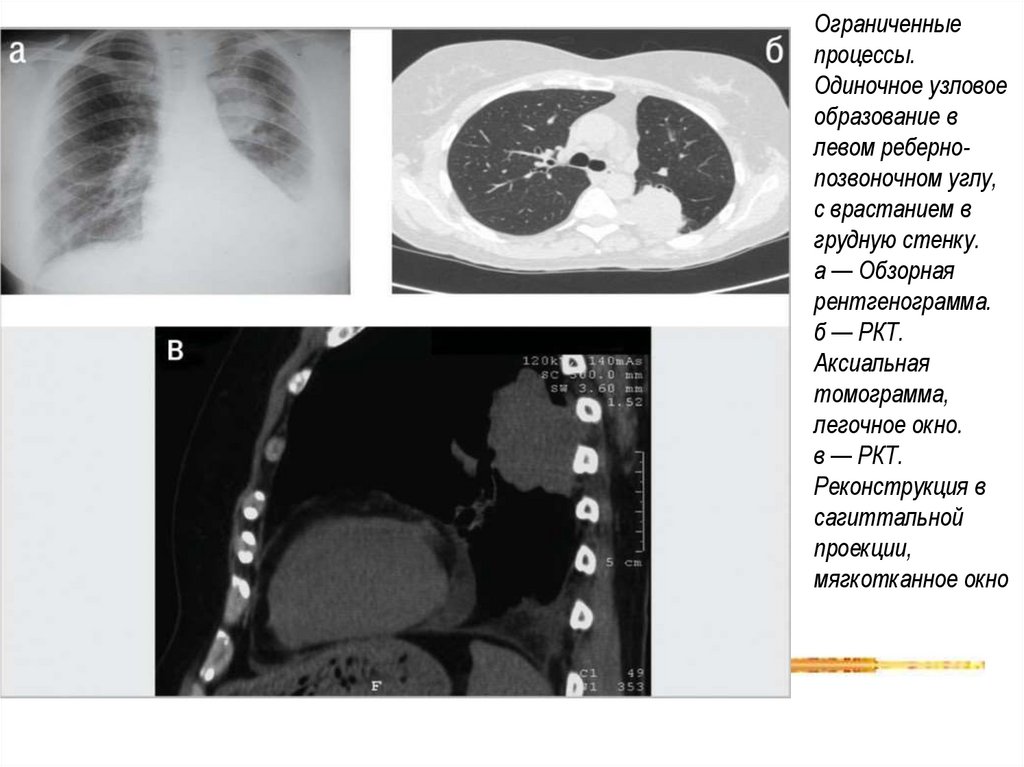

Ограниченные

процессы.

Одиночное узловое

образование в

левом ребернопозвоночном углу,

с врастанием в

грудную стенку.

а — Обзорная

рентгенограмма.

б — РКТ.

Аксиальная

томограмма,

легочное окно.

в — РКТ.

Реконструкция в

сагиттальной

проекции,

мягкотканное окно